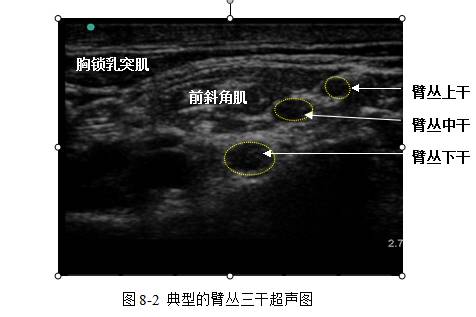

超声引导下区域麻醉/镇痛的专家共识(2014)

置患者于平卧位,需要阻滞侧上肢外展或呈敬礼状,在胸大肌和肱二头肌